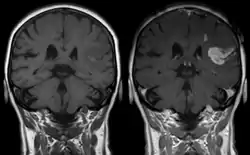

La respuesta de Cushing, también llamada reflejo de Cushing, fenómeno de Cushing o reacción de Cushing, nombrada en honor al neurocirujano estadounidense Harvey Cushing (primero en describir a detalle su fisiopatología),[1][2] es una respuesta fisiológica del sistema nervioso central a la hipertensión intracraneal (HIC) que resulta en la tríada de Cushing: presión sanguínea incrementada, respiración irregular y bradicardia.[3] Normalmente se observa en fases terminales de traumatismos craneoencefálicos agudos y puede indicar herniación cerebral inminente. También se puede observar tras la administración intravenosa de adrenalina y fármacos similares.[4]

Según Rodríguez-Boto, Rivero-Garvía y Márquez-Rivas (2012), la tríada de Cushing se presenta en solo 33% de los casos y no se observa en todos los pacientes con hipertensión intracraneana. La bradicardia por debajo de los 60 latidos por minuto se presenta en solo dos tercios de los casos e hipertensión arterial con PAS superior a 160 mmHG en solo un quinto. Al asociarse con la HIC, «generalmente son tardíos en la evolución del cuadro» y, por ende, implican un «pronóstico ominoso».[3]

La tríada de Cushing es uno de los primeros signos de muerte cerebral inminente y va sucedida por «tormentas adrenérgicas».[5] De acuerdo al propio Cushing, el incremento en la presión intracraneal es la causa primaria de esta respuesta.[2] Los incrementos moderados y continuos en la presión craneal permiten que suceda el reflejo. Sin embargo, los aumentos rápidos no dan el tiempo suficiente para que ocurra.[6]

En 1901, Cushing demostró que, cuando la presión intracraneal se aproxima a la presión arterial media (y hay compresión cerebral y de las arterias cerebrales), se inicia una «respuesta isquémica» que conduce a un incremento de esta última «para mantener una mínima perfusión cerebral». Comúnmente, a este fenómeno (respuesta de Cushing) lo acompañan trastornos respiratorios y bradicardia y en su conjunto forman la tríada de Cushing.[3][7][8]

Ante el incremento de presión, se ve afectado el riego sanguíneo a las neuronas del bulbo raquídeo. «La hipoxia e hipercapnia locales incrementan su descarga», lo que activa los quimiorreceptores centrales localizados en la superficie ventrolateral del bulbo. El resultante incremento en la presión arterial sistémica «tiende a restaurar el flujo sanguíneo» a esa región cerebral. Además, «induce un descenso reflejo de la frecuencia cardíaca», es decir la bradicardia.[9] Esta respuesta «protege a los centros vitales del cerebro de la pérdida de nutrientes en caso de que la presión del líquido cefalorraquídeo sea suficientemente alta para comprimir las arterias cerebrales».[8]